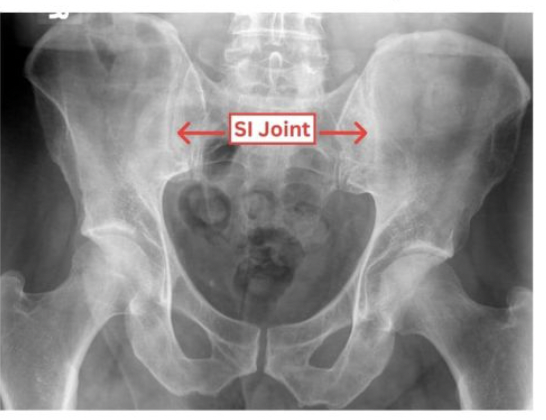

Sacrolititis

normal SI joint